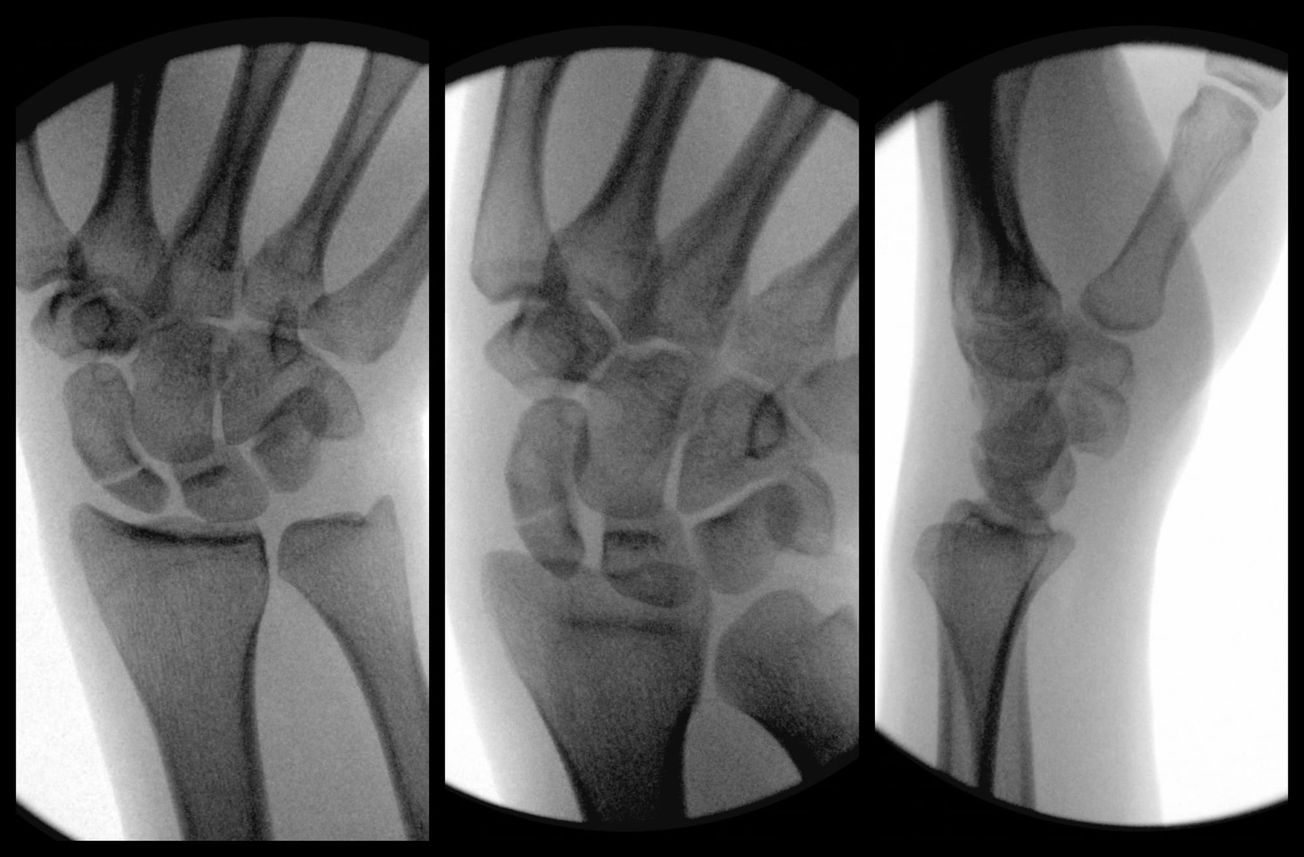

Hand Scaphoid Fracture Fixation , and David Chen , and Omar Nazir , and Adam Mirarchi December 13, 2025